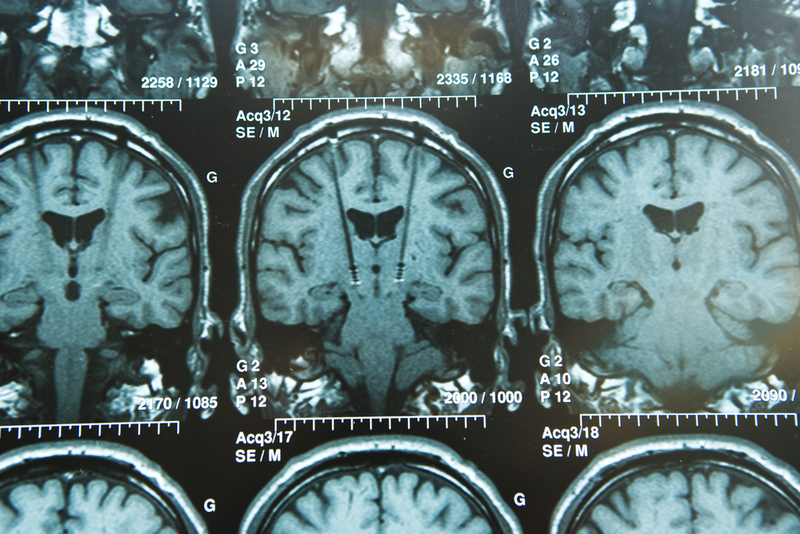

Doctors at Chennai-based MGM Healthcare, have performed Tamil Nadu’s and South India’s first Deep Brain Stimulation (DBS) surgery for Obsessive Compulsive Neurosis or OCD, a mental illness. The procedure was led by Dr. K. Sridhar, Senior Consultant Neurosurgeon at MGM Healthcare and his team of experts.

Deep Brain Stimulation allows people to potentially reduce their medications and improve their quality of life. Explaining the surgery, Dr. Sridhar said, “Deep Brain Stimulation is a type of surgery where micro-electrodes are placed in specific parts of the brain to stimulate groups of nerve cells and their connections. The surgery is done most often for Parkinson's disease and other abnormal movements like Dystonia.

Disclaimer: Image used is for illustrative purposes only and does not represent a true or accurate depiction of the news report.